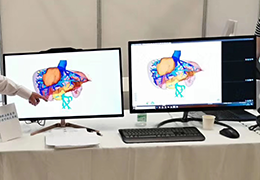

Side-by-side comparative assessment for pre- and post-operative scans.